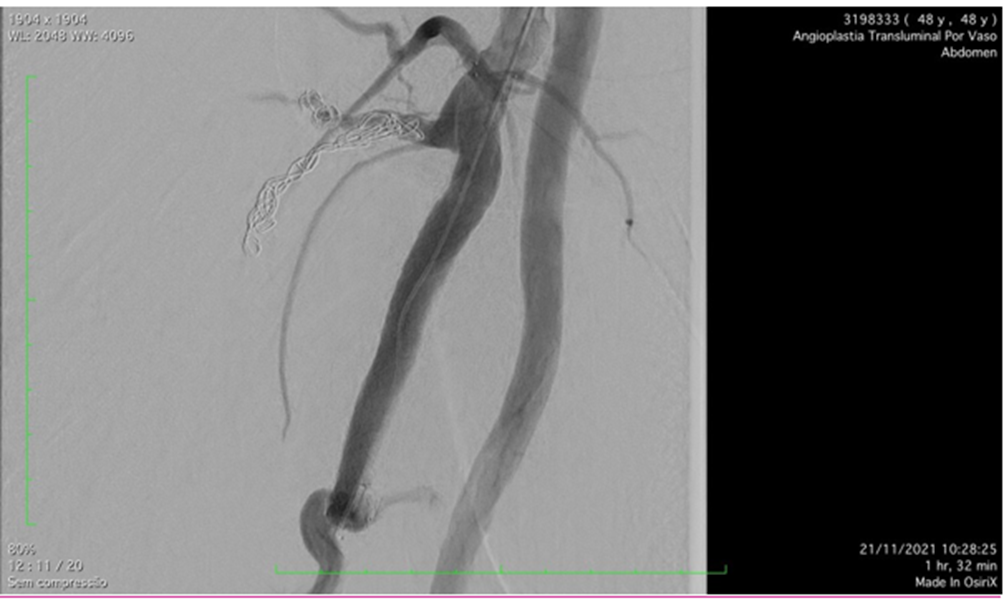

Figure 4: Post-operative arteriography showing covered self-expandable 9x100 Solaris â into the Deep femoral artery.

The patient was scheduled to undergo endovascular treatment of the deep femoral artery aneurysm. Under general anesthesia, a left common femoral artery was punctured guided with a duplex ultrasound., with a 6f 11cm sheath. We decided to use a contralateral access and perform the whole intervention percutaneously. After the puncture, the Perclose Proglide â was inserted, in order to preload and guarantee the sealing of the puncture. Then, a 0,035”260cm Terumo â was passed untiused to perform the crossing overl of the aorta, and a 9F 11cm sheath was placed through the left common femoral artery. The patient was heparinized with 5000UI intravenous in bolus., and the aorta was crossed with an internal mammary 6F catheter alongside the 0,035”260cm Terumo â. We performed a right limb arteriography to confirm the deep femoral artery aneurysm (Figure 3s 5 and 6). The deep femoral artery was properly catheterizedselected with a Headhunter catheter 5F. After this, and we changed the guidewire for an Amplatz 0,035”260cm, in order to place a 55cm 9F delivery system catheter until the origin of the right deep femoral artery. In the arteriography, we have identified a larger branch emerging from the first portion of the deep femoral artery, and we have decided to embolize this branch, to avoid endoleak type II, since it was a larger branch. The microcatheter Progreat â 2,7F alongside the microguidewire Avigo â was used to select the branch. We embolized this branch with Azur â coils 2 4x5, 6x10, 6x15 and 6x20 (figures 7 and 8). After the successful embolization, a covered self-expandable 9x100 Solaris â (Scitech Medical, Brasil) was placed under roadmap into the proximal and distal deep femoral artery aneurysm, and post dilatated with a 9x80 catheter balloon Oceanus â (figure 4 Figures 9 and 10). There were no endoleaks, and the deep femoral artery patency was identified. All the materials were removed, and we completed the final step of the perclose Proglide â puncture closing. The patient was transferred to the room, being discharged from the hospital two days after the surgery with no complications, femoral, popliteal and podal pulses present bilaterally, taking Aspirin 100mg / day and Clopidogrel 75mg/day. After 1 month the patient was evaluated, presenting no further symptoms, no palpable mass in the right groin, and was submitted to a Duplex Ultrasound (Figure 5s 11 and 12), that showed deep femoral artery patency, stent patency, reduction of the aneurysm sac and no endoleaks. Furthermore, after one year follow-up, the patient remained assymptomatic, with Duplex Ultrasound showing deep femoral and stent patency and no endoleaks. (Figure 6).